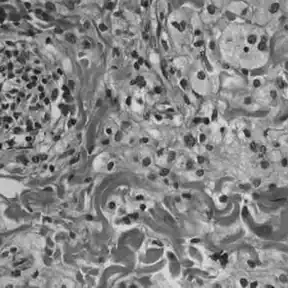

Histologie

La maladie de Chester-Erdheim se distingue de l'histiocytose langerhansienne sur plusieurs points :

- elle n'est pas mise en évidence, contrairement à l'histiocytose langerhansienne, par un marquage à la protéine S-100 ou au CD 1a[13]

- une analyse du cytoplasme en microscopie électronique ne révèle pas de granules de Birbeck[13]

- les échantillons tissulaires montrent des infiltrations xanthomateuses ou xanthogranulomateuses par des histiocytes spumeux (gorgés en graisses), dans un environnement habituellement fibrosé.